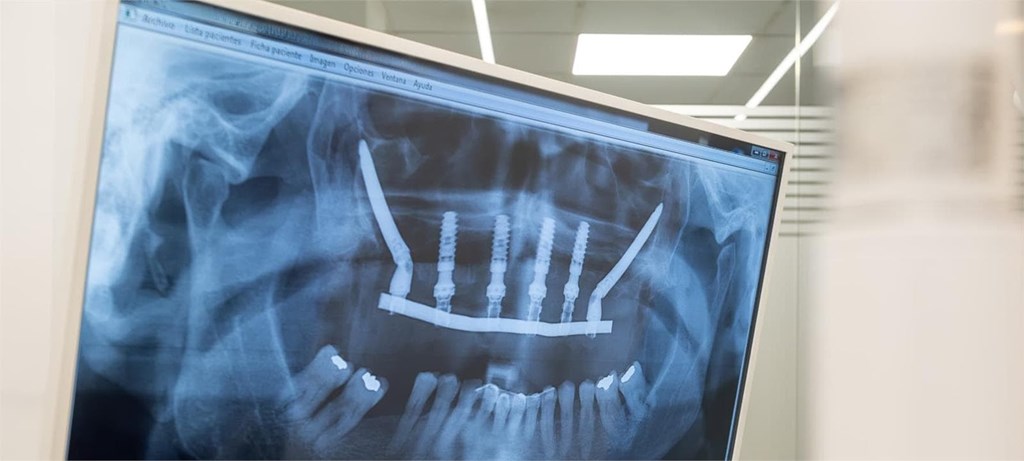

Hoy en día, la implantología ha avanzado tanto que podemos garantizar procedimientos mínimamente invasivos, sin necesidad de abrir la encía ni generar un postoperatorio complicado. ¿El secreto? La tecnología, la formación de nuestro equipo y técnicas como los implantes cigomáticos o el sistema All on 4.

En nuestra clínica dental de Vigo trabajamos con cirugía guiada por ordenador, lo que nos permite colocar los implantes con máxima precisión y sin puntos. Además, gracias a esta tecnología, conseguimos que todo el procedimiento sea más rápido, más cómodo y con una recuperación mucho más rápida. La mayoría de nuestros pacientes salen de la consulta con dientes fijos desde el primer día.